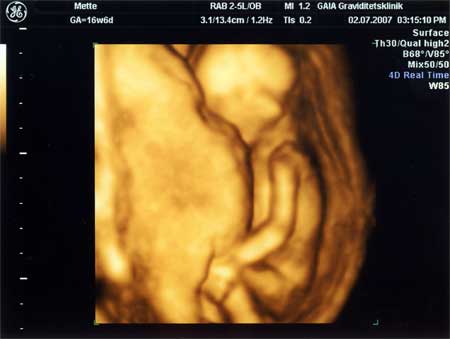

3D scanning – se baby i maven under graviditeten

3d scanning uge 16

3d scanning – uge 16

uge 16+6